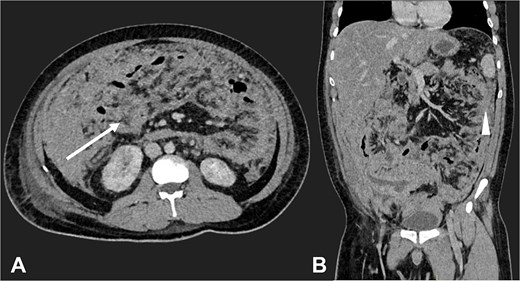

Postoperatively, suspected PTB was evaluated. Diagnostic tests, including sputum smear microscopy and GeneXpert MTB/RIF, peritoneal fluid culture and microscopy, and auramine-rhodamine stool staining, were negative. Thoracoabdominal CT (Figs 2 and 3) revealed generalized PC, plaque-like involvement at the hepatic flexure of the colon, and inflammatory lymph nodes. Histopathology provided the definitive diagnosis of NHL (Figs 4 and 5). Following an uneventful postoperative recovery, the patient was discharged after one week and referred to a tertiary care center, where chemotherapy was initiated, leading to significant improvement.

Contrast-enhanced CT in the arterial phase: Axial view (A) and coronal reconstruction (B) demonstrated mesenteric lymphadenopathy measuring up to 1.53 cm (white arrows).